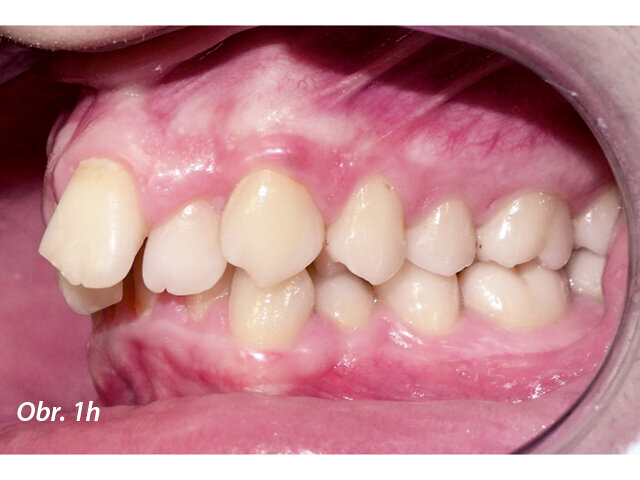

17letý chlapec přišel na konzultaci v prosinci 2014. Při intraorálním vyšetření bylo zjištěno: vztah molárů v I. třídě dle Anglea oboustranně a vztah špičáků v I. třídě vlevo a II. třídě vpravo. Šířka horního zubního oblouku v úrovni molárů byla normální, v místě premolárů však byl zubní oblouk výrazně zúžený a v mezišpičákové oblasti bylo výrazné stěsnání. V dolním zubním oblouku (úzký, tvar paraboly) bylo stěsnání s úplným deficitem místa pro zub 42, který byl v ektopické lingvální poloze. Hloubka skusu byla stoprocentní s traumatickým nákusem do gingivy v okolí dolních frontálních zubů. Zuby horního oblouku byly mírně větší než průměr, s malým nepoměrem Boltonova indexu. Objektivní extraorální vyšetření odhalilo syndrom dlouhého obličeje, vývoj střední třetiny obličeje byl normální a nazální pyramida byla široká ve spojení s mírnou mandibulární retruzí (obr. 1a–h).